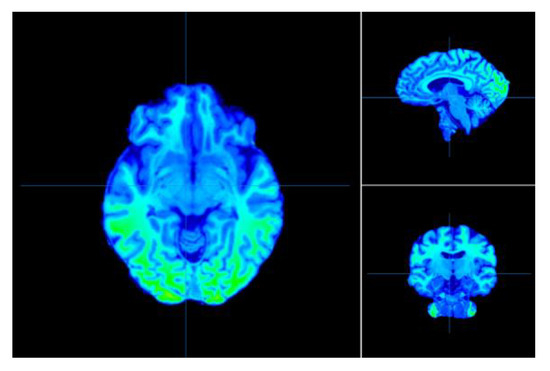

- Metabolic methods, including positron emission tomography (PET) and functional magnetic resonance imaging (fMRI). PET is used to examine the metabolism of glucose within the brain with great accuracy by tracing radiation pulses, while fMRI is used to measure blood flow in the brain to determine changes in brain activity;